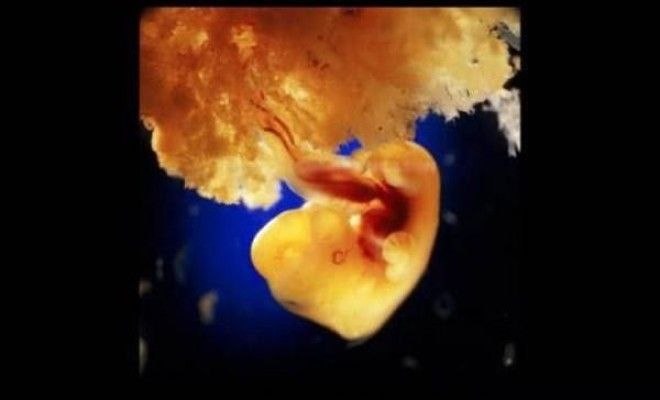

40 дней. Наружные клетки зародыша срослись с рыхлой поверхностью матки и образуют плаценту